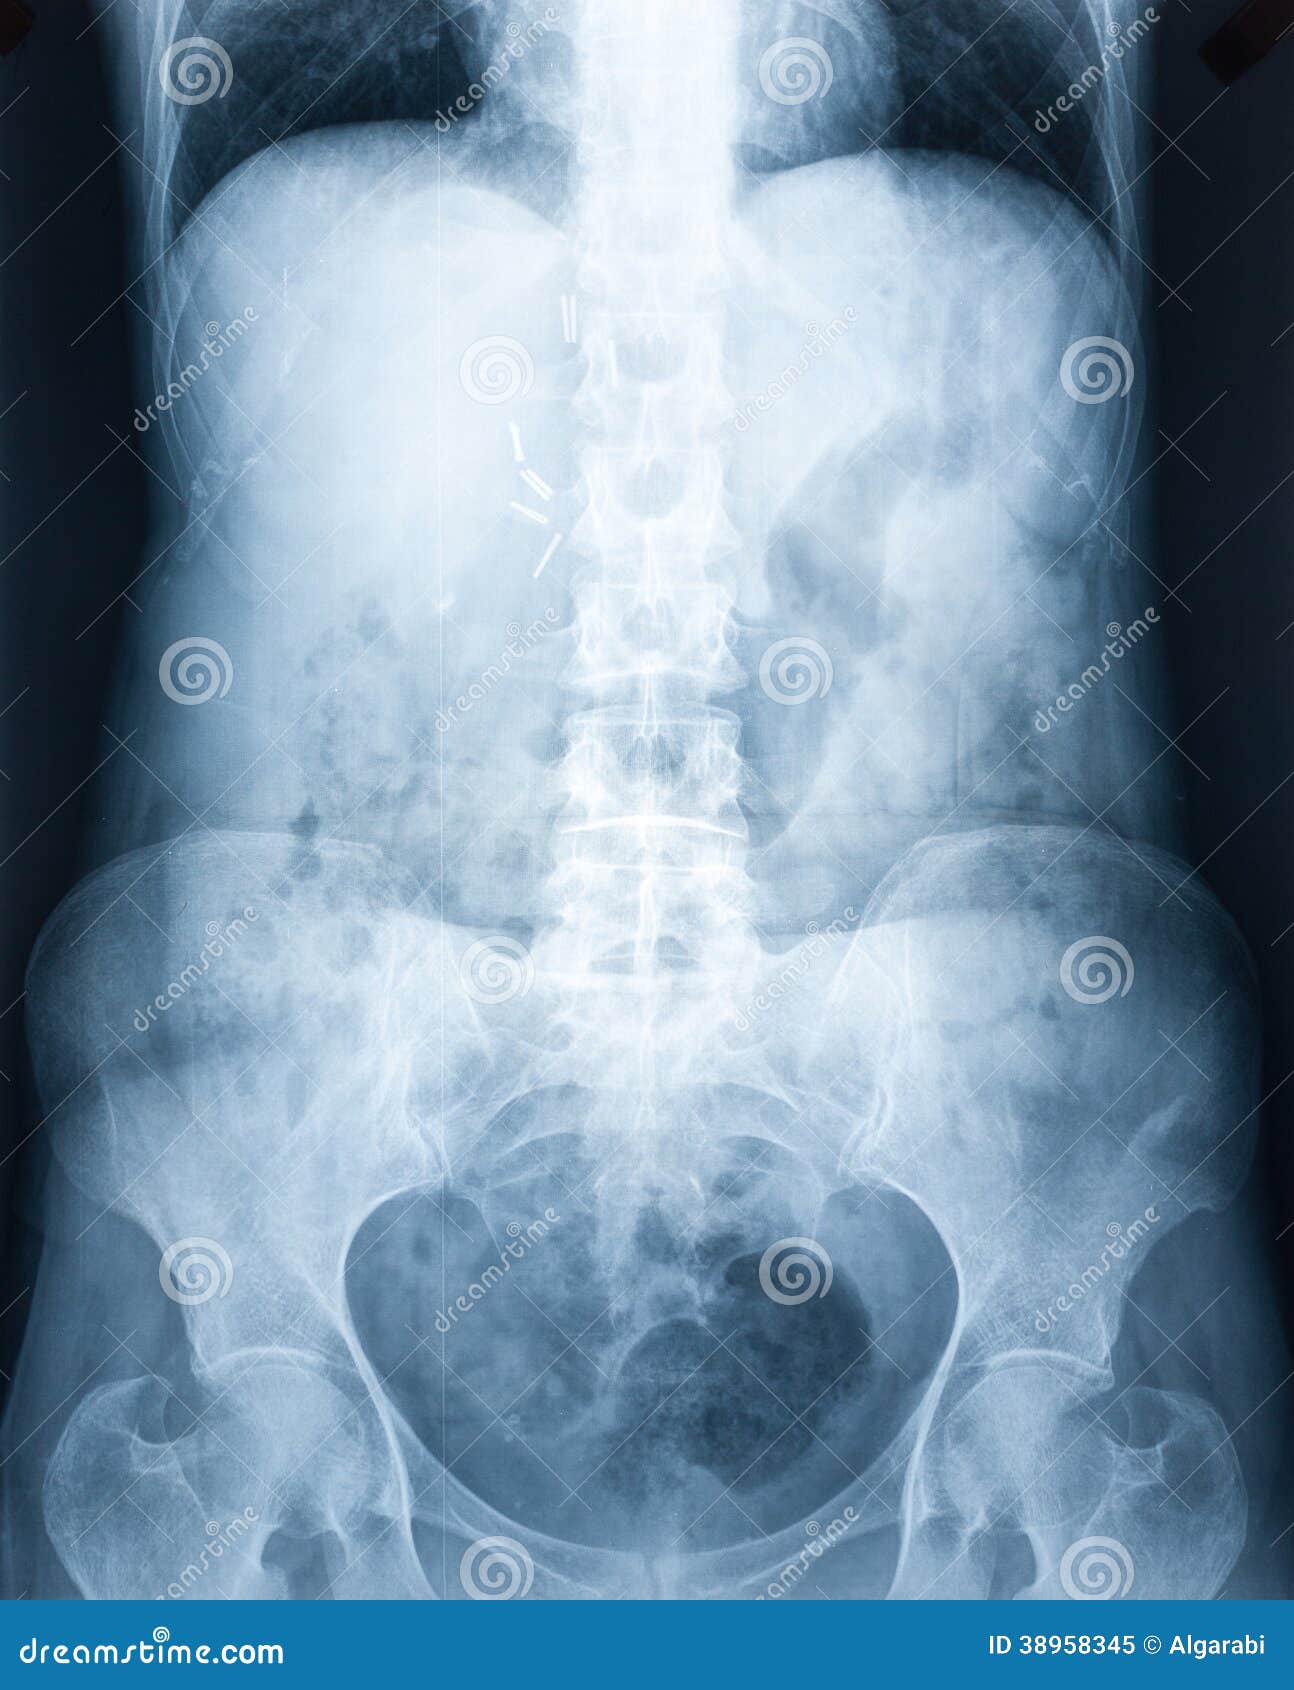

Xray of a human abdomen stock image. Image of diagnostic 38958345 Abdomen Anatomy Xray this involves assessment of the bowel gas pattern, soft tissue structures, and bones. radiology basics of abdominal ct anatomy with annotated coronal images and scrollable axial images to help medical students. it is performed with a higher radiation dose and larger dose of iv contrast, which helps to evaluate subtle areas of bowel. although abdominal radiography. Abdomen Anatomy Xray.